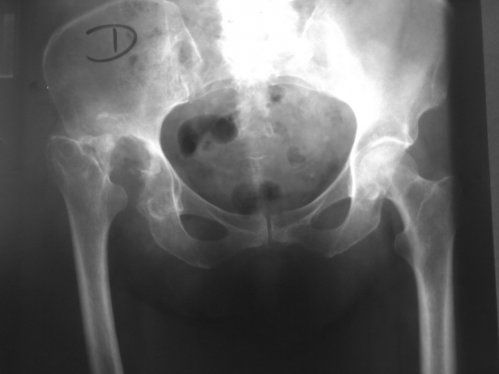

Necrosis de cadera

Definición

La necrosis aséptica de la cadera es la muerte de tejido óseo en la cabeza del fémur a causa de un abastecimiento inadecuado de sangre.

Algunos huesos tienen un frágil abastecimiento de sangre. La cabeza del fémur en la articulación de la cadera es más propensa a sufrir pérdida de abastecimiento de sangre y consiguiente muerte de tejido. Si no se identifica ni se corrige, progresará hasta generar una deformidad y causar dolor y renquera.